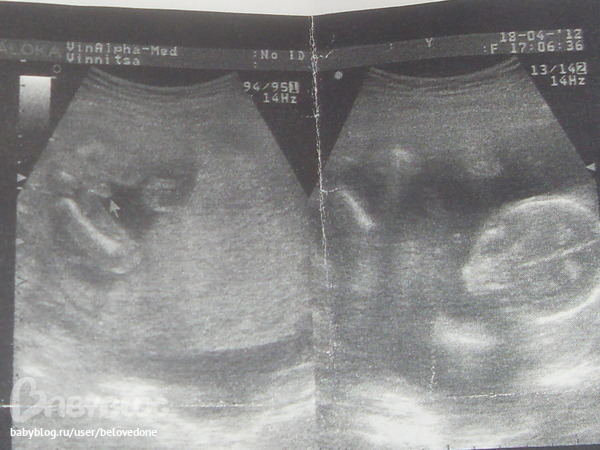

Да писюська наша, обычно на платном долго смотрят, а тогда быстро прошлась по животу сказала что здоровенький мальчик сделала фотку и все.. так что если честно то я не успела и расмотреть ребенка.. Ну конечно и слезы мои я только спросила нет ли грыжи у ребеночка она сказала что все норма и все..

А мне кажется что там писюська мужская точно, форма похожа, если бы бес кончика то думала б что пуповина, а так из за кончика уверена что мальчик.